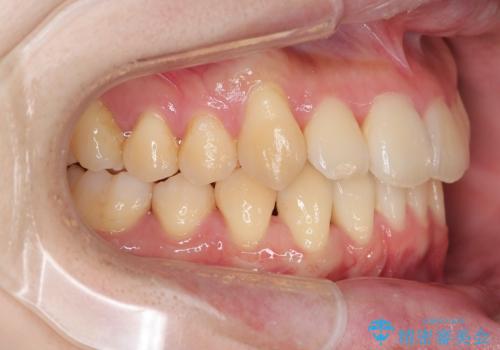

- インビザライン +部分ワイヤー矯正

4本の小臼歯抜歯を避け、下顎前歯の1本抜歯の極力少ない抜歯本数で審美的な歯並びを得る治療計画としました。

すれ違いを治すのが得意な前歯部の部分ワイヤーを用いることで、治療期間を短縮することができました。